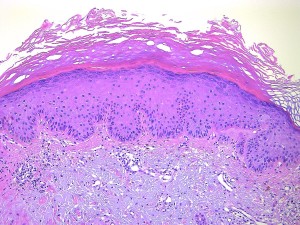

Actinic keratosis (광선각화증)